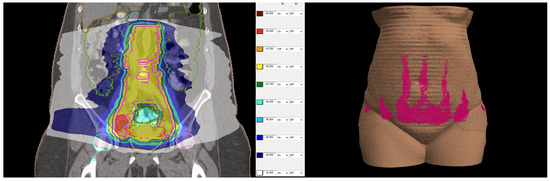

Figure 2.

18-Fluorodeoxyglucose (FDG) PET/CT image before treatment.